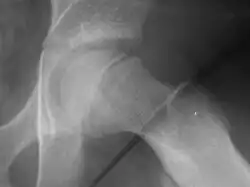

Radiogram of slipped capital femoral epiphysis

Klein's line is a virtual line that can be drawn on an X-ray of a child's hip parallel to the upper edge of the femoral neck. If the line does not intersect with the outermost part of the femoral head 's ball-like end, the diagnosis of a slipped capital femoral epiphysis (SCFE) is confirmed.[1]